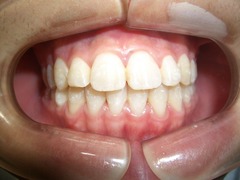

治療終了 2011.12.2 (中学3年生)

1年4ヶ月で終了しました